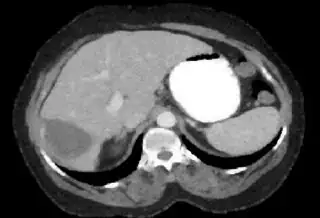

Below I apply two successive morphological openings to the image using a 3x3 circular kernel, and then apply k-means clustering to the gray levels. From your sample images and some I found on the internet, I decided to set k = 4. If you are using high-resolution images, first downsample them to dimensions ~400-600. Otherwise the morphological operation may not have a significant effect, and the k-means will be slow.

Below are some of the opened and segmented images. Of course there's more to be done in terms of

• separating out the liver region

• generalizing this to a large dataset

but hope this is at least a starting point.

Update You might be able to narrow down the region or interest by filtering out the darkest and the lightest regions from the segmented image. For this, use the k-means cluster centers, check for the extreme values (max and min) and remove the corresponding k values from the labeled image. Then you can look for large structures to the left of the result image. Worst case, you might get a hole on the left side when the extreme region filtering goes wrong. I've updated the code and results.